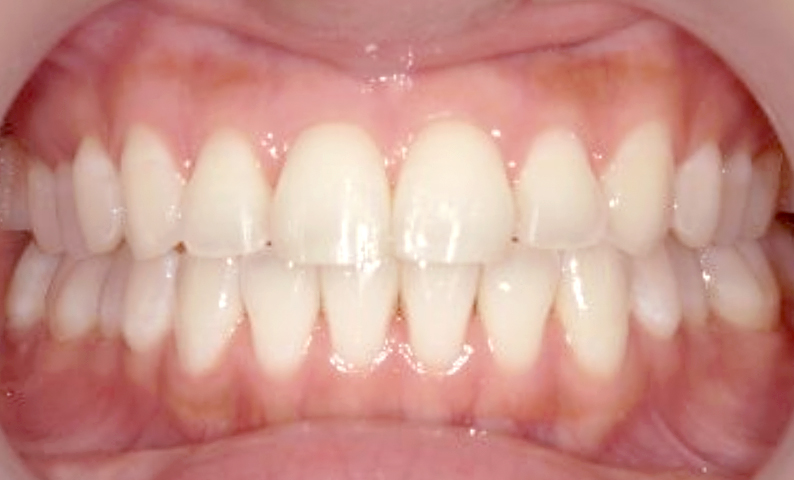

症例_001 前歯「捻転歯」症例

治療期間:6ヶ月金額:48万円+税20代女性少しのねじれ捻転歯下の八重歯

| Before | After |

|---|---|

|